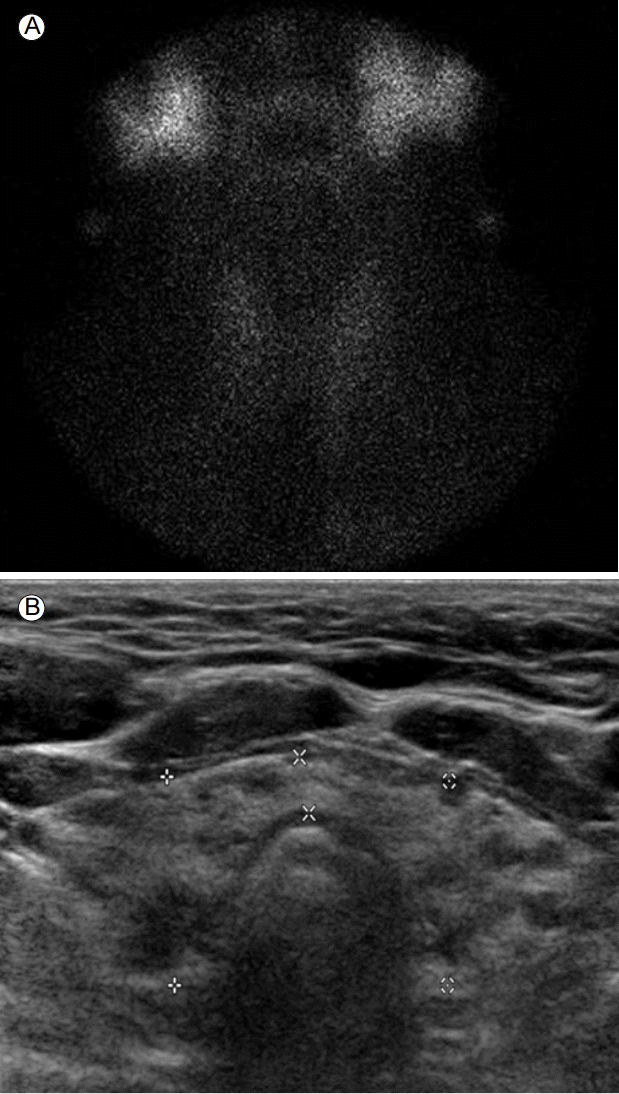

Figure 2.

Tc-99m pertechnetate thyroid scan and ultrasonography. (A) The scan revealed decreased uptake in the thyroid gland. (B) Ultrasonography revealed that both glands were atrophic with a coarse and heterogenetic echogenicity.